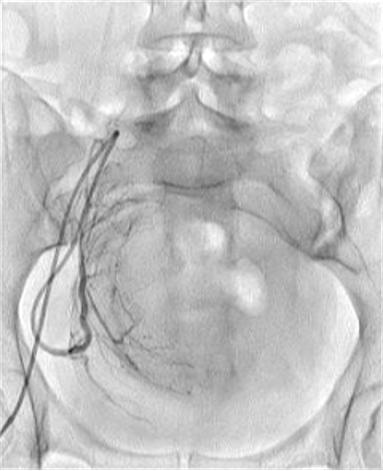

所有年龄超过 40 岁的患者, 卵巢受损 14%-43% 研究中闭经发生率(15%)与单纯UAE报告相似,可能与患者年龄(≥45岁)及卵巢储备自然下降有关。 ![]() 50岁,长期因子宫肌瘤导致月经出血过多,痛经和贫血。 子宫肌瘤栓塞术前,显示双侧子宫动脉发育不全,子宫肌瘤双侧卵巢动脉。 经皮股动脉穿刺双侧卵巢动脉栓塞,先500μm-700μm emboSphere 微球 术后4周,和6月的中短期随访,月经正常,子宫容积减少,贫血纠正,无卵巢功能衰竭。但看起来非灌注容积较少。 术后9月,由于子宫肌瘤持续存在,患者自己希望绝经,行全子宫和双侧卵巢切除术 术后病理,子宫内可见栓塞微粒伴有坏死,卵巢内也见栓塞微粒,但卵巢功能未受损。